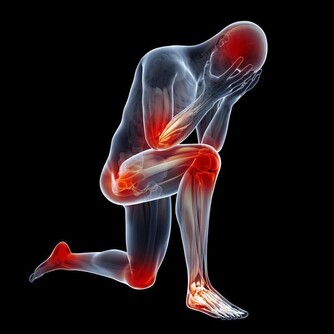

14. 下巴是腎和全身有酸痛的地方;也叫疲勞酸痛區。